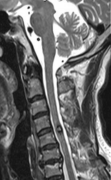

脑海绵状血管瘤全切后还会复发吗? C4-5髓内海绵状血管瘤海绵状血管瘤术后能否恢复?恢复时间大概是多久?术后复发的概率是多少? 杨先生于2年半前开始出现左手虎口至左肘关节上...